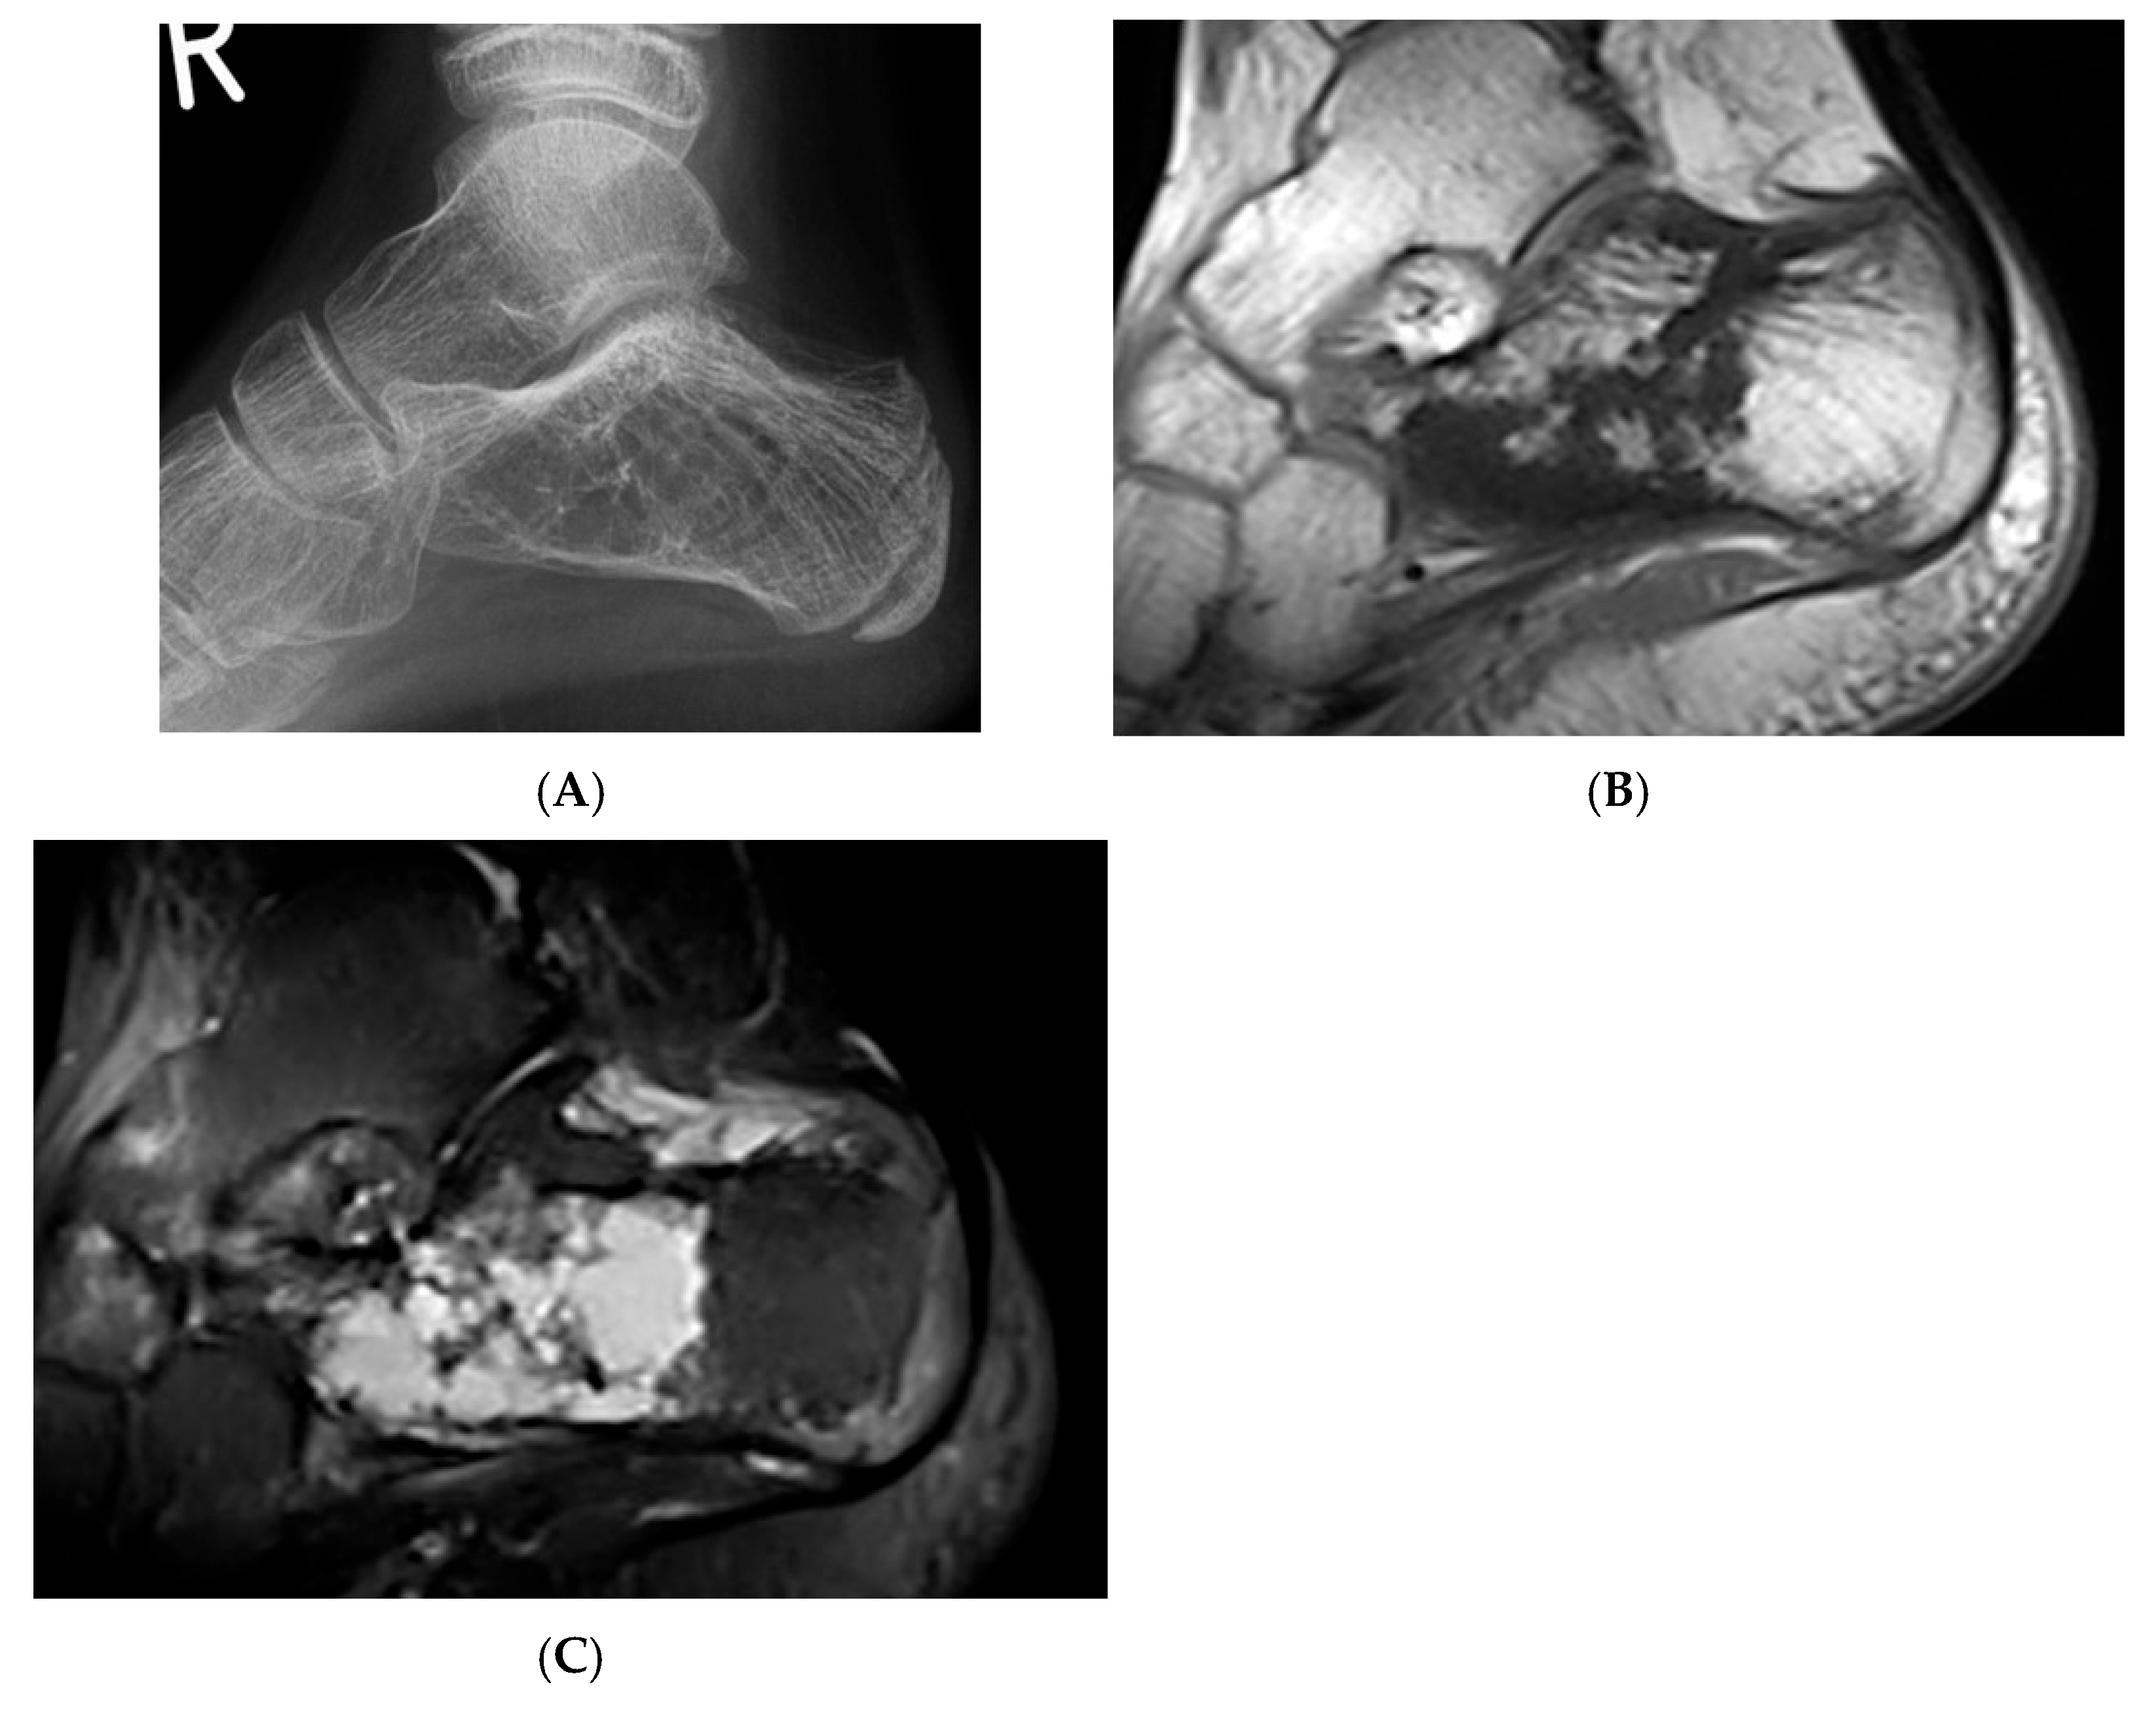

Figure 5.

Haemangioma, calcaneum. (A) Plain radiograph demonstrating honeycomb pattern. (B) Sagittal T1W MRI and (C) sagittal STIR MRI demonstrating intralesional fat component (low T1 and high STIR) and septations.